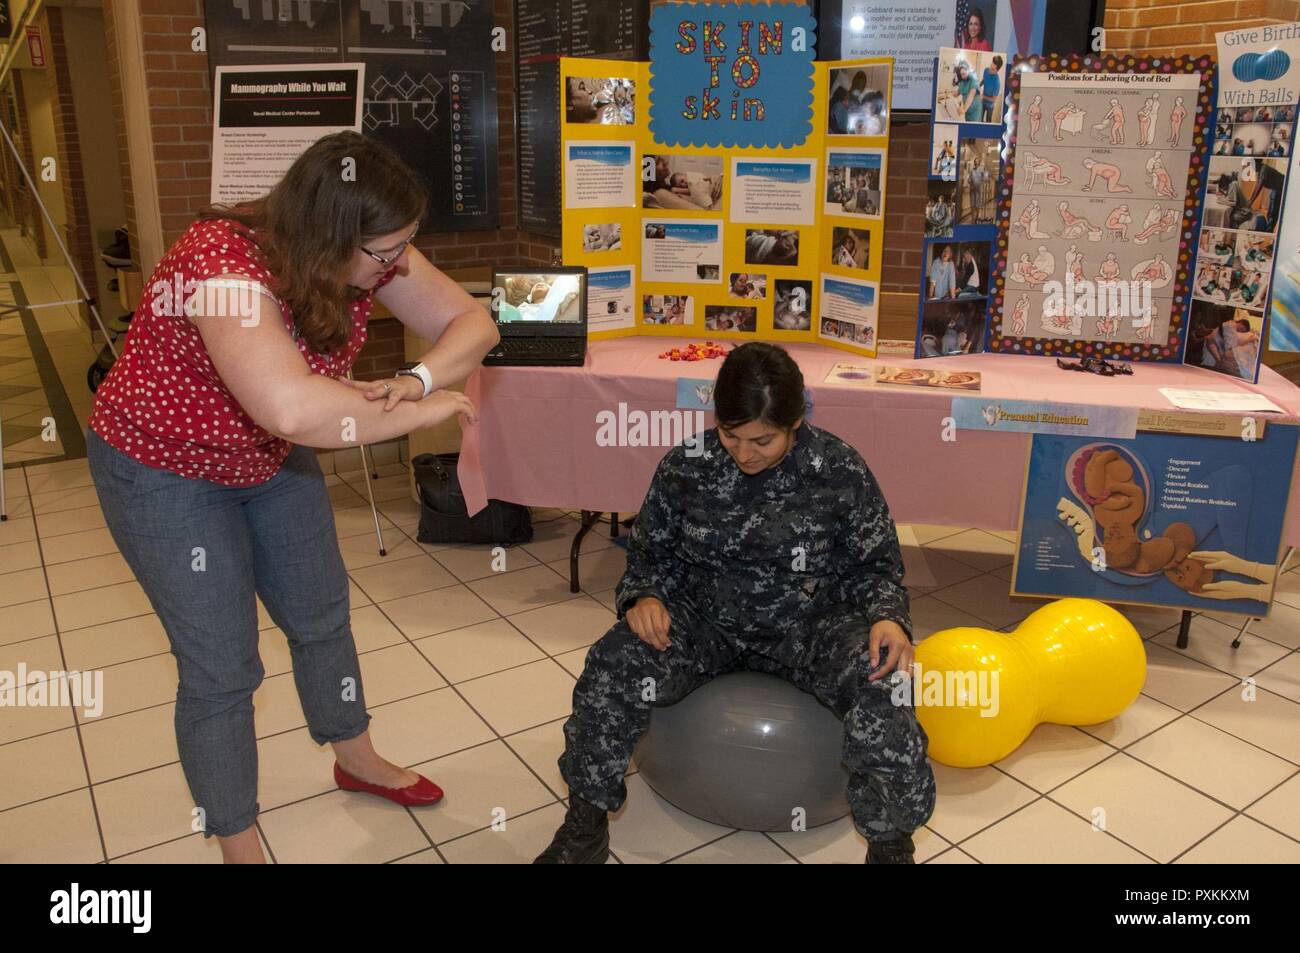

170609-N-GM597-006 Portsmouth, Va. (June 9, 2017) Heather McFarland, left, an outpatient lactation consultant with the Pediatrics Clinic, speaks with a patient about lactation consultant services during the Pregnancy Fair at Naval Medical Center Portsmouth. The Women’s Health Clinic sponsored the fair that offered information on a variety of pregnancy-related topics, including nutrition, exercise, fetal development, birthing positions and lactation. (U.S. Navy photo by Rebecca A. Perron/Released) Stock Photohttps://www.alamy.com/image-license-details/?v=1https://www.alamy.com/170609-n-gm597-006-portsmouth-va-june-9-2017-heather-mcfarland-left-an-outpatient-lactation-consultant-with-the-pediatrics-clinic-speaks-with-a-patient-about-lactation-consultant-services-during-the-pregnancy-fair-at-naval-medical-center-portsmouth-the-womens-health-clinic-sponsored-the-fair-that-offered-information-on-a-variety-of-pregnancy-related-topics-including-nutrition-exercise-fetal-development-birthing-positions-and-lactation-us-navy-photo-by-rebecca-a-perronreleased-image186589936.html

170609-N-GM597-006 Portsmouth, Va. (June 9, 2017) Heather McFarland, left, an outpatient lactation consultant with the Pediatrics Clinic, speaks with a patient about lactation consultant services during the Pregnancy Fair at Naval Medical Center Portsmouth. The Women’s Health Clinic sponsored the fair that offered information on a variety of pregnancy-related topics, including nutrition, exercise, fetal development, birthing positions and lactation. (U.S. Navy photo by Rebecca A. Perron/Released) Stock Photohttps://www.alamy.com/image-license-details/?v=1https://www.alamy.com/170609-n-gm597-006-portsmouth-va-june-9-2017-heather-mcfarland-left-an-outpatient-lactation-consultant-with-the-pediatrics-clinic-speaks-with-a-patient-about-lactation-consultant-services-during-the-pregnancy-fair-at-naval-medical-center-portsmouth-the-womens-health-clinic-sponsored-the-fair-that-offered-information-on-a-variety-of-pregnancy-related-topics-including-nutrition-exercise-fetal-development-birthing-positions-and-lactation-us-navy-photo-by-rebecca-a-perronreleased-image186589936.htmlRMMRFWA8–170609-N-GM597-006 Portsmouth, Va. (June 9, 2017) Heather McFarland, left, an outpatient lactation consultant with the Pediatrics Clinic, speaks with a patient about lactation consultant services during the Pregnancy Fair at Naval Medical Center Portsmouth. The Women’s Health Clinic sponsored the fair that offered information on a variety of pregnancy-related topics, including nutrition, exercise, fetal development, birthing positions and lactation. (U.S. Navy photo by Rebecca A. Perron/Released)

170609-N-GM597-039 Portsmouth, Va. (June 9, 2017) Norma Dawn Knight-Pongratz, a perinatal educator, shows Interior Communication Electrician 3rd Class Madai Cooper how the birthing ball can relieve back pain during the Pregnancy Fair at Naval Medical Center Portsmouth. The Women’s Health Clinic sponsored the fair that offered information on a variety of pregnancy-related topics, including nutrition, exercise, fetal development, birthing positions and lactation. (U.S. Navy photo by Rebecca A. Perron/Released) Stock Photohttps://www.alamy.com/image-license-details/?v=1https://www.alamy.com/170609-n-gm597-039-portsmouth-va-june-9-2017-norma-dawn-knight-pongratz-a-perinatal-educator-shows-interior-communication-electrician-3rd-class-madai-cooper-how-the-birthing-ball-can-relieve-back-pain-during-the-pregnancy-fair-at-naval-medical-center-portsmouth-the-womens-health-clinic-sponsored-the-fair-that-offered-information-on-a-variety-of-pregnancy-related-topics-including-nutrition-exercise-fetal-development-birthing-positions-and-lactation-us-navy-photo-by-rebecca-a-perronreleased-image186589941.html

170609-N-GM597-039 Portsmouth, Va. (June 9, 2017) Norma Dawn Knight-Pongratz, a perinatal educator, shows Interior Communication Electrician 3rd Class Madai Cooper how the birthing ball can relieve back pain during the Pregnancy Fair at Naval Medical Center Portsmouth. The Women’s Health Clinic sponsored the fair that offered information on a variety of pregnancy-related topics, including nutrition, exercise, fetal development, birthing positions and lactation. (U.S. Navy photo by Rebecca A. Perron/Released) Stock Photohttps://www.alamy.com/image-license-details/?v=1https://www.alamy.com/170609-n-gm597-039-portsmouth-va-june-9-2017-norma-dawn-knight-pongratz-a-perinatal-educator-shows-interior-communication-electrician-3rd-class-madai-cooper-how-the-birthing-ball-can-relieve-back-pain-during-the-pregnancy-fair-at-naval-medical-center-portsmouth-the-womens-health-clinic-sponsored-the-fair-that-offered-information-on-a-variety-of-pregnancy-related-topics-including-nutrition-exercise-fetal-development-birthing-positions-and-lactation-us-navy-photo-by-rebecca-a-perronreleased-image186589941.htmlRMMRFWAD–170609-N-GM597-039 Portsmouth, Va. (June 9, 2017) Norma Dawn Knight-Pongratz, a perinatal educator, shows Interior Communication Electrician 3rd Class Madai Cooper how the birthing ball can relieve back pain during the Pregnancy Fair at Naval Medical Center Portsmouth. The Women’s Health Clinic sponsored the fair that offered information on a variety of pregnancy-related topics, including nutrition, exercise, fetal development, birthing positions and lactation. (U.S. Navy photo by Rebecca A. Perron/Released)